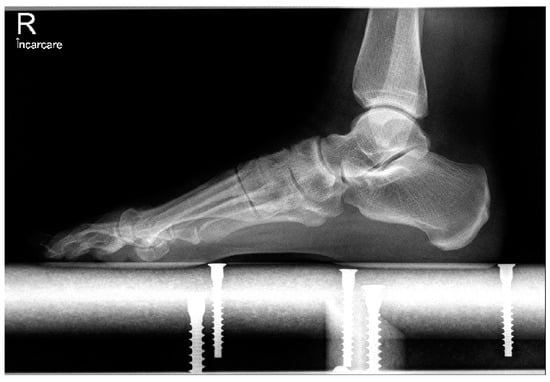

In the open chevron osteotomy group, a 5 cm dorsomedial incision was made. The V-shaped osteotomy was performed using a motor-driven saw. The osteotomy was created in 60 degrees with an angled chevron, and the tip of the osteotomy was positioned 2 mm proximal to the anatomical center of the metatarsal head. The metatarsal head was repositioned in a lateral direction and directly inspected through the incision. The osteotomy was then fixed using a 3.0 mm cannulated screw. The adductor hallucis tendon was released from the fibular sesamoid through a 15 mm dorsal incision. For both groups, the skin was closed using separate 2-0 sutures, and a soft bandage was applied. Postoperative treatment consisted of soft dressings applied weekly. After 3 weeks, the sutures were removed. Full weight-bearing on the forefoot was avoided by wearing an orthosis for six weeks (Figure 3, Figure 4 and Figure 5).

From a radiological standpoint, both groups demonstrated improvements regarding the IMA and HVA at the last follow-up. We did not find any significant differences between the groups at the final assessment (Table 2).

Figure 4. Postoperative oblique image after 12 months.